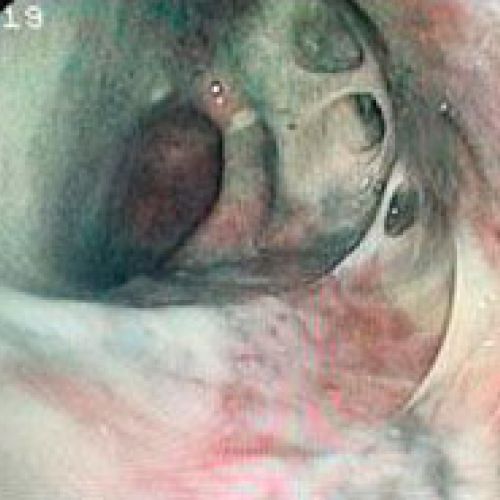

Endoscopia rígida y endoscopia flexible

En CiruVET realizamos procedimientos diagnósticos, como las endoscopias de última generación

En CiruVET contamos con el equipo necesario para los diferentes procedimientos diagnósticos y terapéuticos a nivel respiratorio y digestivo. En resumen, realizamos las siguientes pruebas diagnósticas: